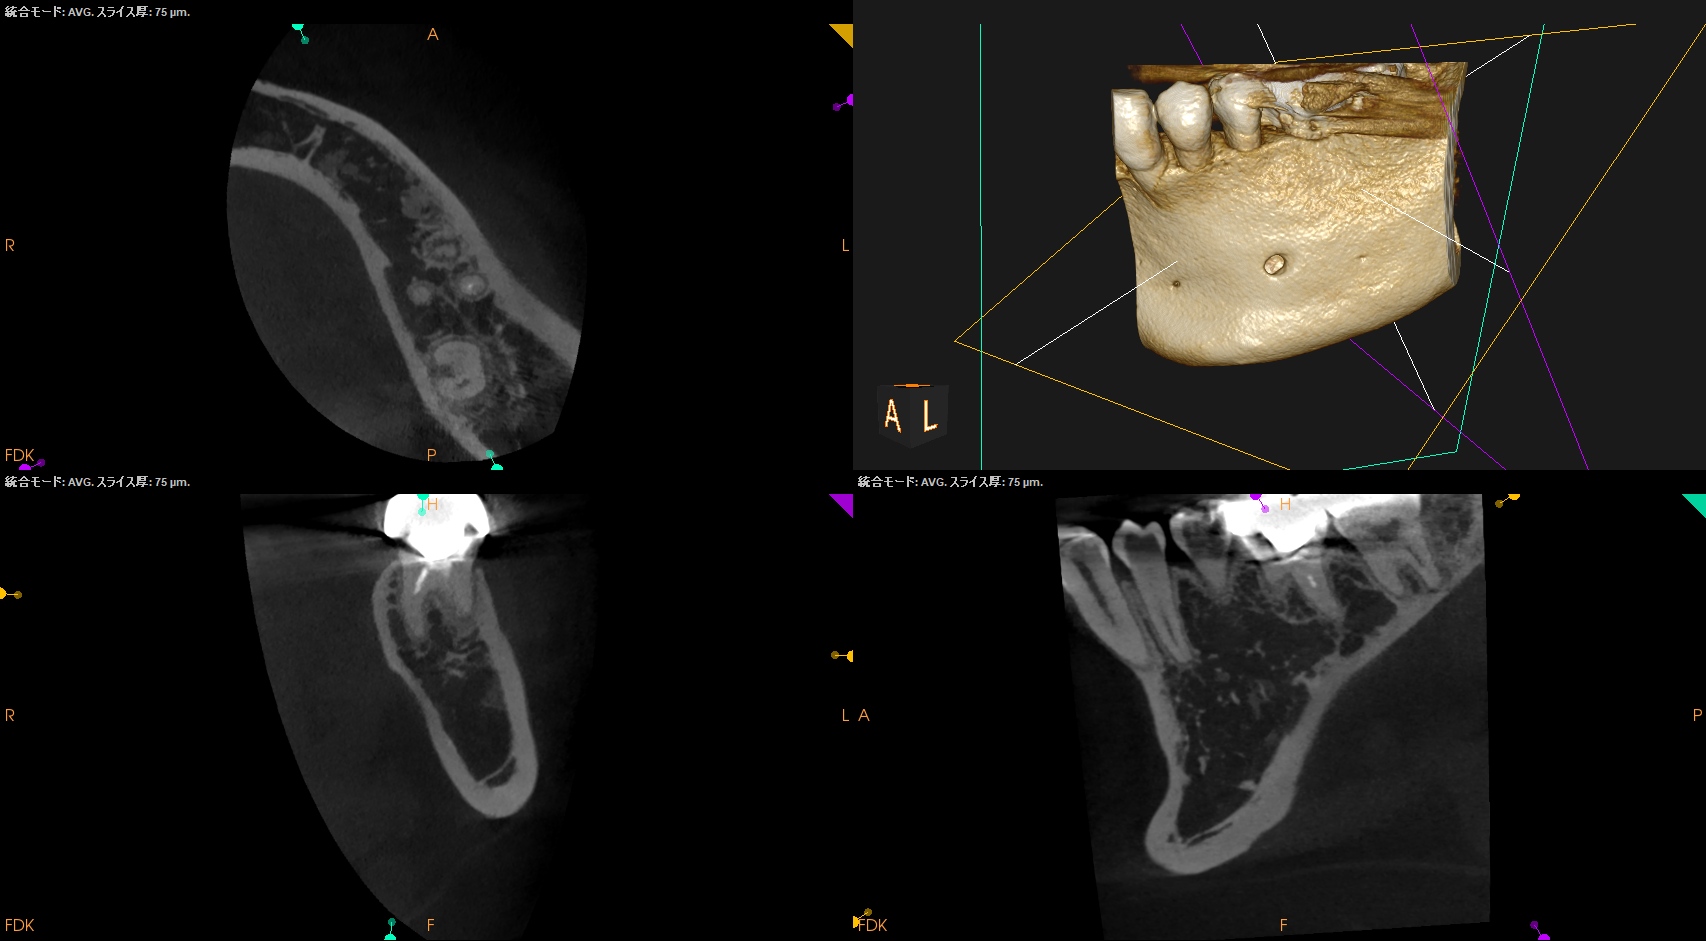

ではCBCTはどうだろうか?

#19 MB

#19 ML

MBとMLの間にはMMがあるようだ。

CBCTだとここまで術前にわかる。

#19 MM

そしてApex付近に病変がある。

MMが未形成で根尖病変ができている。

ここは攻略が必要そうだ。

#19 D

#19 Radix

D,Radixには病変がない。

術後にPA, CBCTを撮影した。

湾曲が強いことがわかるだろう。

そしてこのMMもML寄りにあることがわかる。